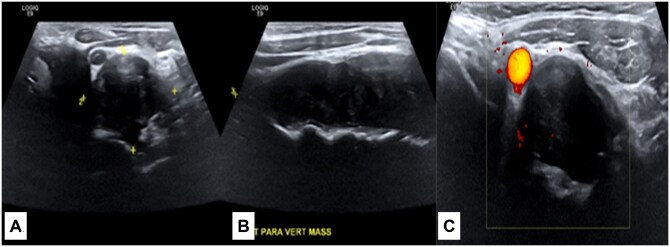

Desmoid tumours are rare benign tumours that show locally aggressive and invasive features leading to potential complications. They can be quite challenging for the treating surgeon if they occur adjacent to neurovascular structures. The aetiology of these tumours is still unclear, but the incidence is higher in females and in patients with a history of trauma or surgical procedures, raising the possibility of genetic and hormonal factors as well as post-traumatic or post-operative inflammatory changes promoting the formation of desmoid fibromatosis. We report a case of a 34-year-old Asian female who presented to our hospital with a history of difficulty in swallowing due to an enlarging lump on the left side of her neck. Patient had a past medical history of previous cervical spinal disc surgery due to a herniated disc. Diagnostic imaging showed a large soft tissue mass centred between the left common carotid artery and the cervical vertebrae displacing the trachea and oesophagus to the right side. A biopsy was obtained, and histopathological examination was suggestive of a desmoid tumour. The patient underwent surgical resection of the tumour but returned later with recurrence and had to undergo the surgery again to achieve full cure.